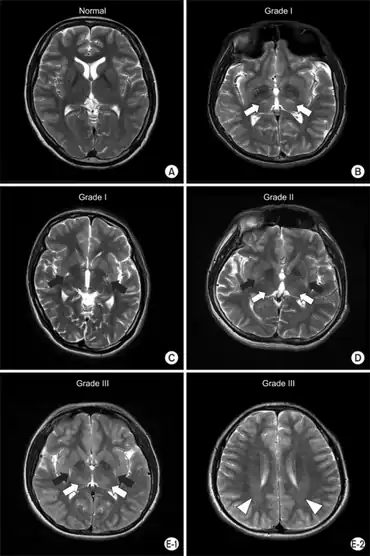

| Muscles innervated by the accessory nerve | |